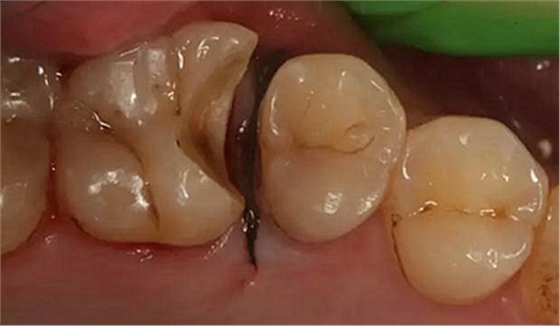

最后附幾例一次性根管治療+冠延長手術(shù)+高嵌體修復(fù)的病例,均為兩次完成。第一次就診:根管治療一次完成,后冠延長手術(shù),然后高嵌體預(yù)備,取模,第二次就診,拆線,試戴嵌體。具體在此不做詳細(xì)說明,圖中有詳解。

另外一個病例